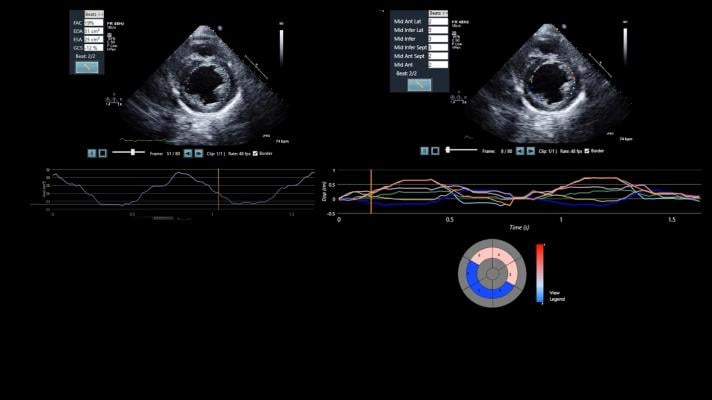

LVivo SAX uses artificial intelligence (AI) to analyze segmental left ventricle wall motion using the parasternal short axis view. This is a common cardiac view used in point-of-care ultrasound settings, as it provides views of cardiac tissue supplied by all three major coronary vessels and is relatively easy to acquire without manipulating the patient’s posture. The LVivo SAX tool is designed to provide medical clinicians with varying levels of ultrasound analysis or cardiological experience the ability to automatically measure, track and evaluate cardio functions, and to detect abnormalities that reduce variability and increase efficiency.

Emergency room and point-of-care clinicians typically order an electrocardiogram (ECG), a blood test and an ultrasound when a patient presents with ACS symptoms. The ultrasound images, which are vitally important given that ECG and blood tests are not always conclusive, are typically viewed visually. The results are often dependent on the clinician’s level of training and experience. As an integrated part of an ultrasound and information technology (IT) system, LVivo SAX leverages AI to bring objectivity to the process to provide an automated and objective assessment of left ventricular function and segmental function.